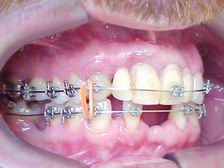

Extrusão completa do canino reanatomizado trans-cirurgicamente

Lado esquerdo: Alinhamento e nivelamento em evolução